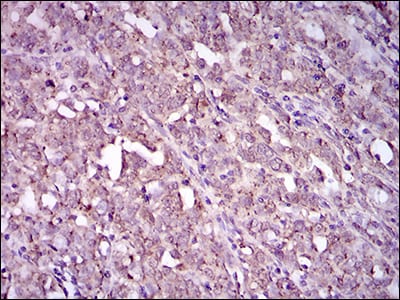

分类: 科研抗体货号: 30504别名: GSC应用: IHC,FCM反应种属: Human